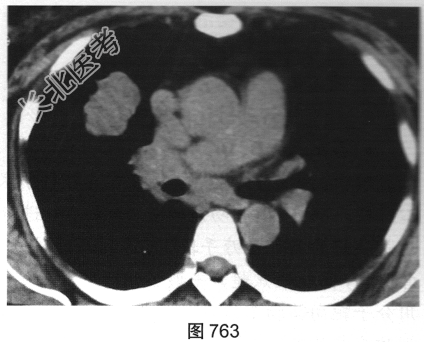

- 多项选择题2.[提示]患者行胸部CT检查,如图762、图763所示。胸部CT如图所示, 超声心动图显示心功能降低,冠状动脉CTA除显示原支架内轻度狭窄外, 未见其他异常。为明确病变性质,下一步应进行哪些检查( )